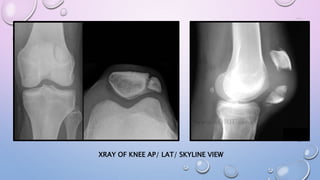

XRAY OF KNEE AP/ LAT/ SKYLINE VIEW

FRACTURE AROUND KNEEJOINT- XRAY OF KNEE AP/ LAT

XRAY OF KNEEAP/ LAT/ SKYLINE VIEW